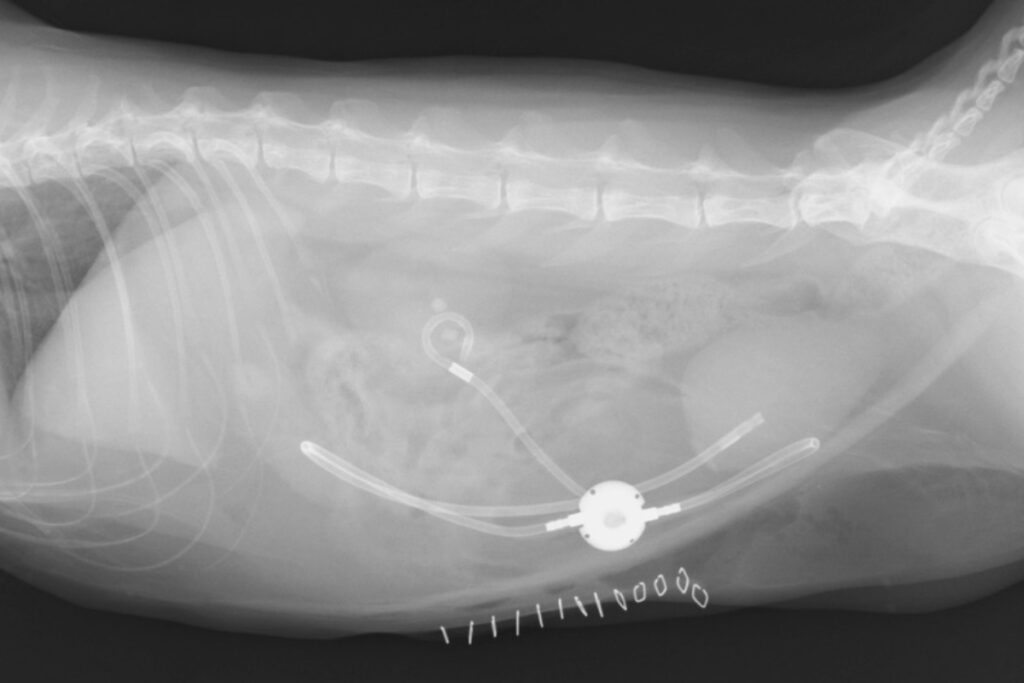

腎臓から尿道にかけての様々な部位における外科手術など幅広く対応しております。尿管結石の症例に対しては、尿管切開術や腎瘻チューブ設置術などからSUBシステムの設置術など症例によって様々対応ができるようにしております。また、近位の尿管結石のような自己組織のみでの尿路の再建が難しい症例に対しても、膀胱弁形成(Boari flap, Modified boari flap)やRenal descensusなどを併用して尿管膀胱新吻合術を行うことで人工物を使わない手術の対応も症例によっては実施可能です。